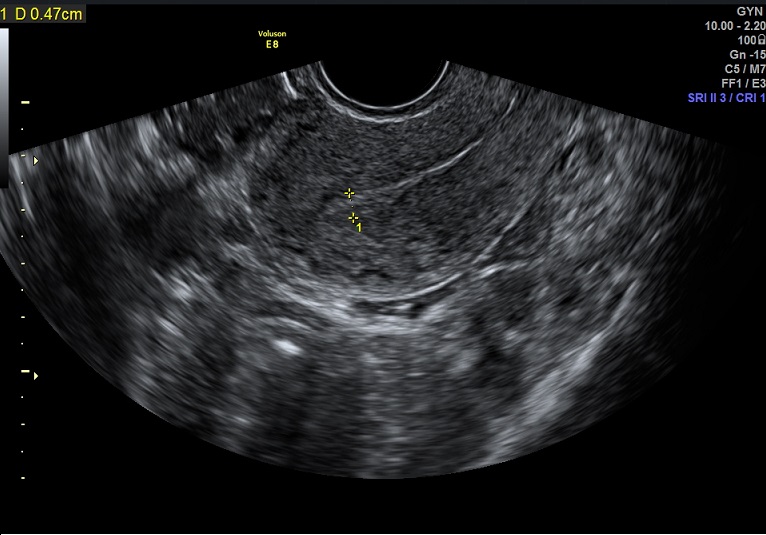

| 女性,25岁,继发性不孕1年余,难免流产4次。 | ||

2015-1-26 月经第23天检查 黄体期 |

2015-1-26图示